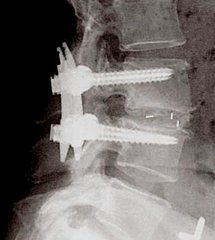

开放手术,切口较大,能彻底切除椎间盘,然后进行椎体间融合,这个节段椎间盘不会再有突出,因为这个间隙的椎间盘已经被彻底摘除干净,而且两个椎体之间进行了融合(两个椎体长到了一起),不再有活动。但邻近节段椎间盘退变会加快,有可能会相继出现椎间盘突出。